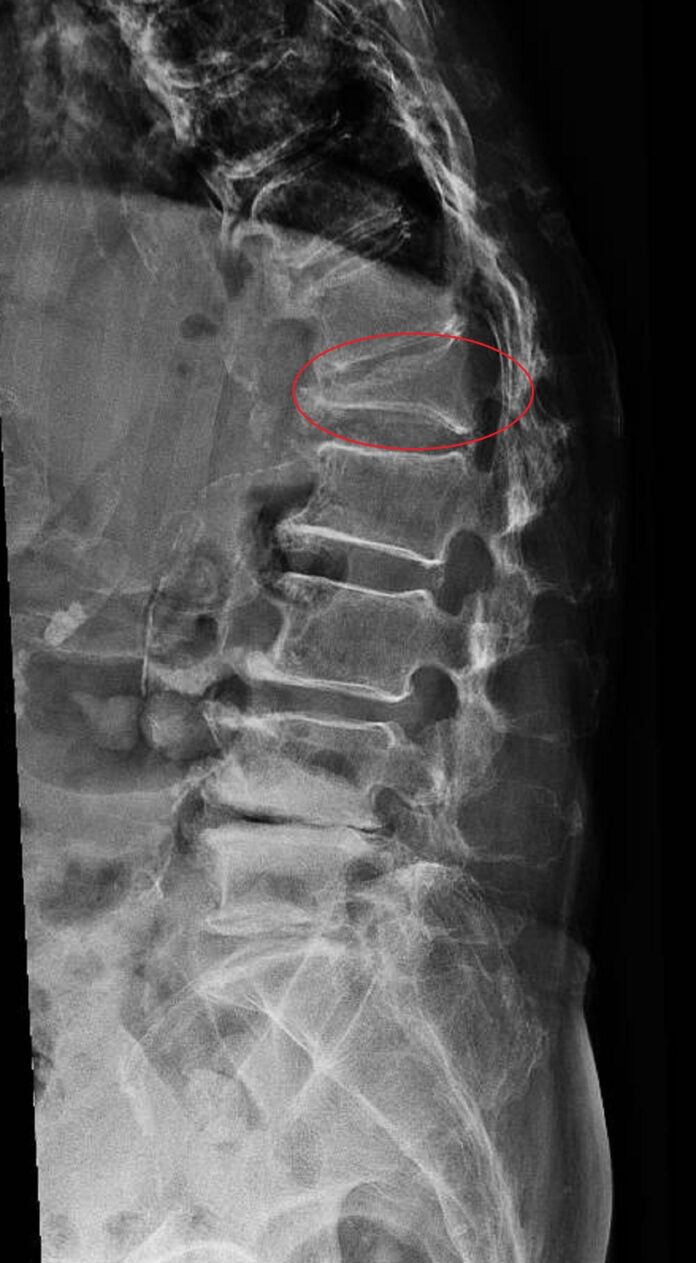

洪宗賢表示,X光及核磁共振影像可看出阿嬤的腰椎第一節的脊椎壓迫性骨折,長方體的椎體擠壓成三角體,短時間造成脊椎椎體完全崩塌,駝背達50度,一般而言,角度達到40度即為駝背,可見椎體壓迫程度很大。

洪宗賢指出,他對陳姓阿嬤施以微創人工骨泥椎體形成術,採用骨水泥灌注以及椎體支架,合併健保申請的脊椎骨釘及支架,以微創手術的方式固定,病人術後疼痛明顯緩解,駝背順利矯正回35度,住院5天順利出院。